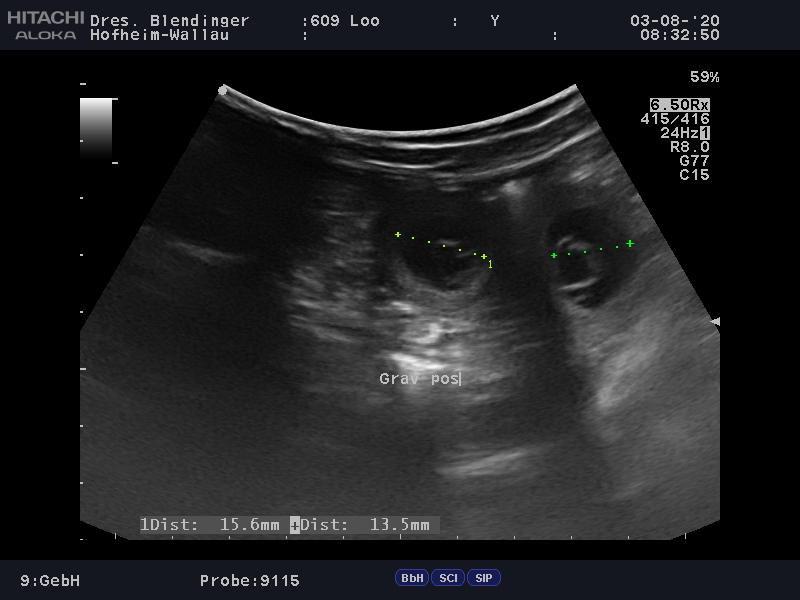

07.08.2020 - Ultraschalluntersuchung

Laut Ultraschall hat unsere "Solero des Teutones" Tochter "Malimaniac's Dynamite"

nach "Malimaniac's Erlkönig" (Hermann de Alphaville Bohemia x Gemfire the Flying Eagle) aufgenommen.

Wir freuen uns riesig auf unseren J-Wurf.